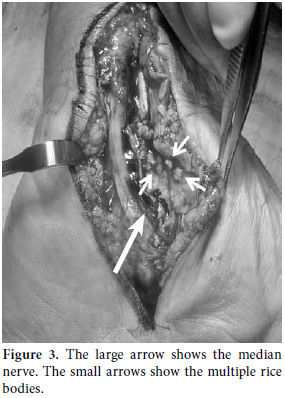

A 48-year-old male was treated at another health center for a year due to painless swelling over the volar region of the left wrist. He also had paresthesia and numbness in the median nerve distribution of the hand and forearm before coming to our clinic. There were no constitutional symptoms or past history of major illness, but he was known to be an alcoholic. Surgery had been performed twice by the primary physician at the other clinic based on a misdiagnosis of a volar wrist ganglion. A physical examination revealed non-tender, fluctuant swelling over the volar aspect of the left wrist. The overlying skin appeared normal, and there was limited flexion of the wrist joint. The swelling extended through the carpal tunnel and ended at the mid-palm. Plain radiographs of the wrist and chest were normal, and laboratory findings, which included the erythrocyte sedimentation rate (ESR), were within normal limits. Magnetic resonance imaging (MRI) of the left wrist revealed tenosynovitis of the flexor digitorum superficialis and profundus. It was decided that surgical intervention via a synoviectomy was the best course of action because of the swelling around the tendon sheaths. A classic, lengthened carpal tunnel incision was performed which allowed for the decompression of all of the affected tendon sheaths (Figure 1). At the beginning of the operation, a swollen capsular mass was detected on the proximal edge of the wound that mimicked volar wrist ganglia. The capsule was opened, the cold abscess-like fluid drained, and rice bodies were detected. The swollen capsular mass was suspected to be a part of tuberculous tenosynovitis (Figures 2 and 3). Afterwards, a complete tenosynovectomy with extensive debridement of the surrounding granulation tissue and carpal tunnel decompression was performed (Figure 3), and the wound was then primarily closed. Mycobacterium tuberculosis was isolated on a culture, and a histopathological examination revealed caseous necrosis with granuloma formation (Figure 4). The patient received anti-TB chemotherapy for nine months, which included ethambutol, pyrazinamide, rifampicin, and isoniazid for the first three months and only isoniazid and rifampicin for the next six months. Follow-up examinations were conducted at two month intervals, and at two years postoperatively, the patient was found to be symptom free, with full range of motion in the wrist joint. No recurrence was detected.

Two main views are common in the literature regarding the so-called rice bodies that are associated with TB. Some studies have indicated that they can be found around the tendon sheaths, but this is a rare occurrence related to rheumatoid arthritis (RA)[14] in which they can be seen within the joints or bursae. In addition, rice bodies can also be observed in cases of systemic lupus erythematosus (SLE), seronegative arthritis, infectious arthritis (TB, atypical mycobacterial infection) nonspecific arthritis, and osteoarthritis (OA).[14-19] However, Woon et al.[20] reported that finding rice bodies along with millet seed or melon seed-shaped lesions is highly suggestive of tuberculous tenosynovitis. They also suggested that the surgeon has to be aware of the significance of loose bodies when performing a routine excision of innocuous looking wrist ganglia.